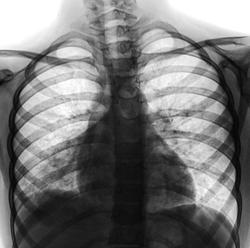

Ребенок направлен на рентгенографию ОГК с подозрением на правостороннюю пневмонию.

Не  вижу  пневмонии.

Что-то вижу справа в нижней доле …, но в позитиве лёгочную патологию анализировать непривычно. А переводить в негатив времени нет пока.

Правостороняя нижнедолевая пневмония........похоже, и плеврит есть справа. Да, смотреть неудобно в позитиве, мне непривычно, да и с размерами - так мелко, а при увеличении в экран монитора не влезает ((((

Правосторонняя н/долевая, но учитывая размеры сердца, корни, возможно застойная. Соорентируйтесь по клинике. Может быть и два в одном.

Пневмонии тоже не вижу. Соглашусь, что хотелось бы посмотреть оригинал в негативе, а не позитив с усилением резкости. От цифрового шума лёгочный рисунок очень пестрит. Справа наслоение усиленного рисунка на рёбра. Сердце "расширено" вправо за счёт поворота ребёнка, но всё равно правое предсердие подозрительное....

при наличии соответствующей клиники и лабораторной картины - поставил бы правостороннюю нижнедолевую

С детьми не работаю. Насчёт пневмонии утверждать не буду. Не нравиться косая полоса идущая от сердца, может быть ателектаз или плеврит.

Если присмотреться, то снижение прозрачности сводится к местам пересечения ребер и усиленного лёгочного рисунка. Есть небольшие продолговатые зоны сниженной воздушности, которые, скорее всего, являются дольковыми микроателектазиками на фоне нарушенной бронхиальной проходимости. Явления бронхита имеются однозначно. Та косая полоса справа - это изменённый корень с периваскуляным отёком и перибронхиальными изменениями. У детей картина всегда более "яркая" и "пугающая". К тому же, она очень быстро меняется и на фоне такого бронхита до пневмонии рукой подать. Лечение принципиально отличаться не будет, а в случае затяжного течения необходимо повторить снимок.

Мне не нравится место, обведенное красным овалом, отчетливо видна разница в пневматизации на уровне межпозвонковых дисков вверху и внизу. Возможно, здесь даже осумкованный паракостальный задний плеврит. Но могу ошибаться. Вот бы КТ сделать.

в легких имеются с обеих сторон. Нарушение бронхиальной проходимости сегметов нижней доли справа с объемным уменьшением. Явное повышение прозрачности верхней доли справа. Корень левого легкого расширен, малоструктурен. Определяется деформация, обогащение прикорневого легочного рисунка. Характер подобных изменений может иметь место при осложненном течении туберкулеза внутригрудных лимфатических узлов. Предполагаю, что ребенок имеет семейный контакт с больными туберкулезом.

На мой взгляд, однозначно была. Все же думаю ателектаз или гиповентиляция нижней доли.